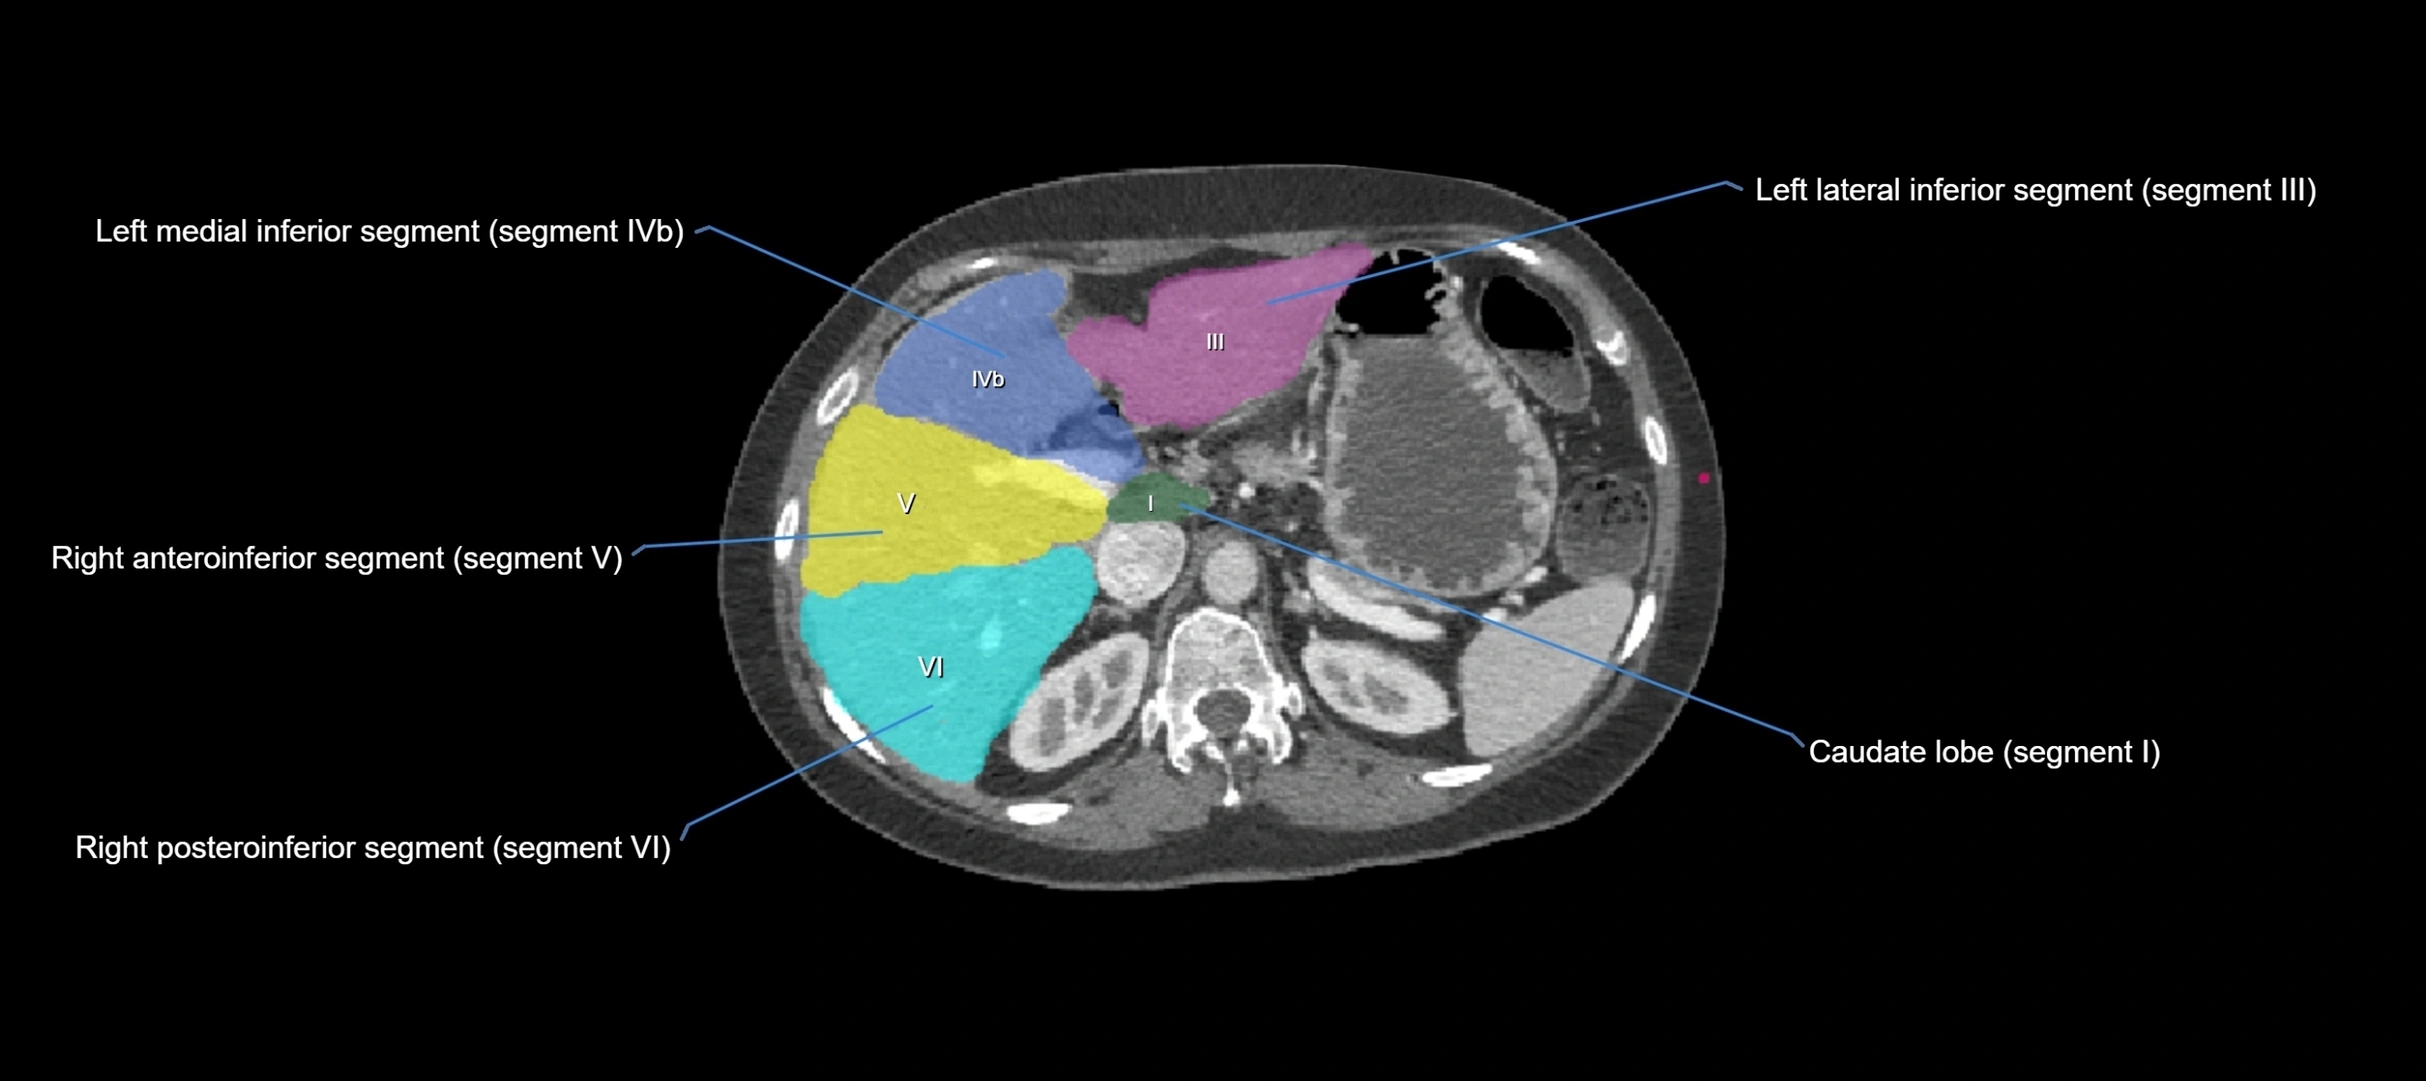

CT Image

image